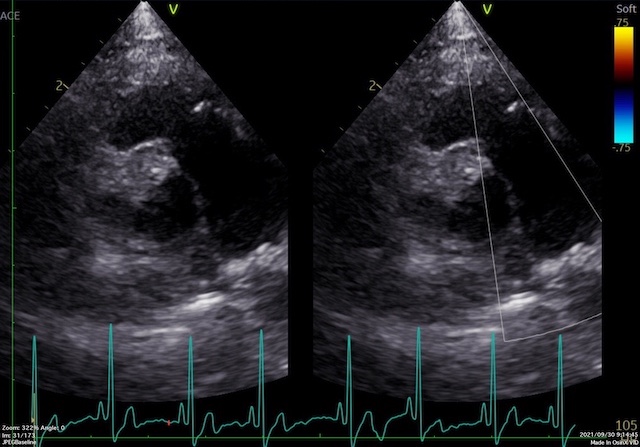

まずこれが術前の写真

僧帽弁の前尖の逸脱が激しく、血液の逆流が酷く認められます。咳が酷く、運動するとすぐ疲れてしまうような臨床症状も出ておりました。利尿剤を投与するも心拡大は酷くなる一方でしたので、手術となった症例です。

続いて、術後の写真

術後は弁の逸脱が抑えられており、血液の逆流もほぼなくなりました。咳嗽の症状もなくなり、活発に運動できているようです。